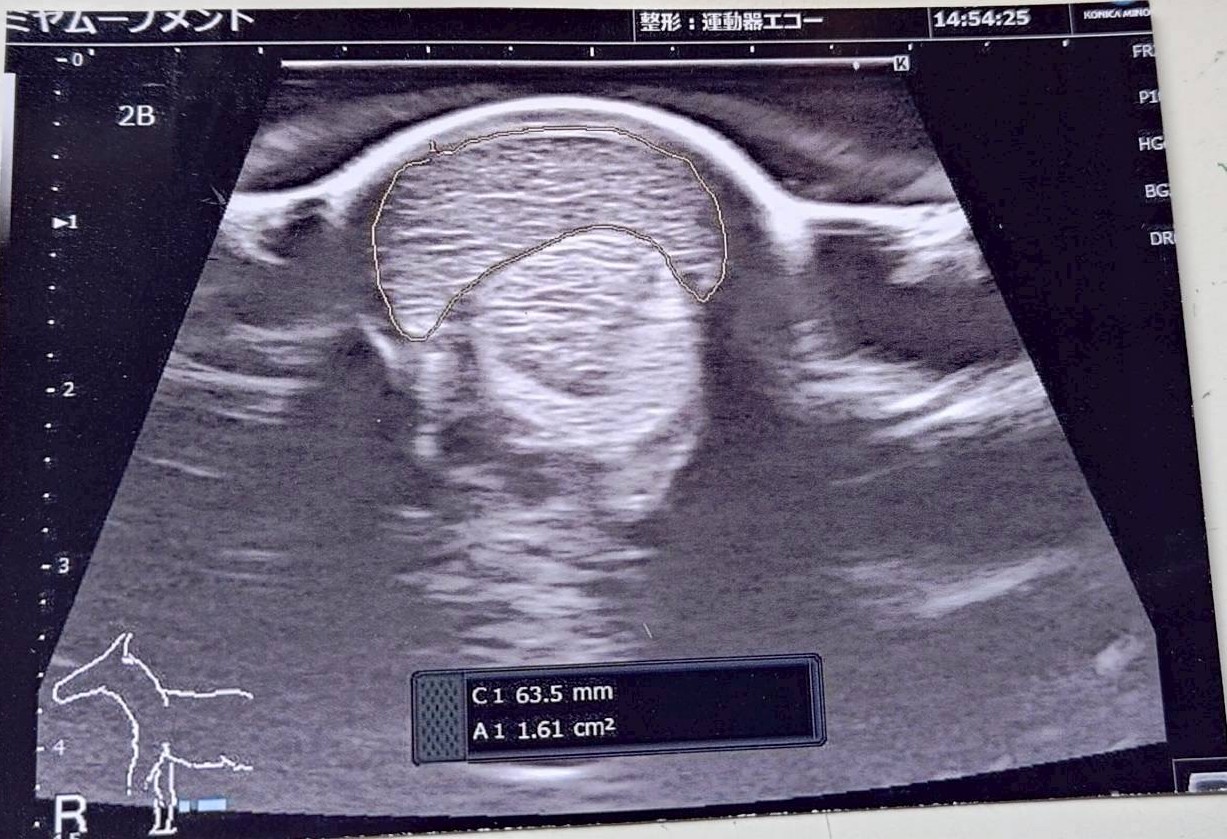

なお前走後に両前肢のエコー検査を行ったところ、腱に損傷は見られないものの腱が太くなっているので注意が必要との診断でした。